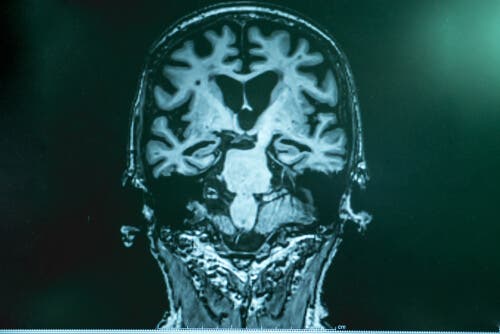

Dr. Lopera forklarer, at der, med Alzheimers sygdom, er en form for ophobning af “skrald” i hjernen. Det udgøres af et protein ved navn amyloid. Fragmenter af det klistrer sig sammen og skaber en form for “lim”, der klistrer sig til neuronerne og forårsager en række af malfunktioner i hjernen.

Den anden del af “skraldet” er tau, hvilket vikler sig rundt om neuronerne, “fanger” dem og dræber dem. Tau er mere skadeligt.

Efter omhyggelige studier i Boston, fandt eksperter ud af, at patientens hjerne var fyldt med amyloid, endnu mere end i andre tilfælde. Dog, havde hun meget lidt tau. Forskningen gjorde det muligt for dem at bekræfte, at en anden mutation, hos denne særlige patient, forhindrede produktionen af tau. Det var det, der forsinkede udviklingen af sygdommen.